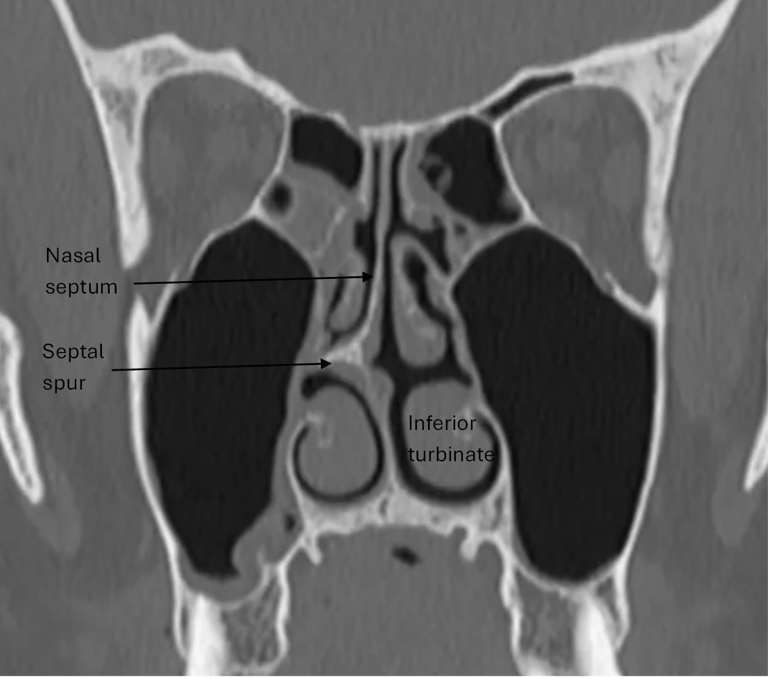

Nerves in the nasal mucosa are compressed due to a deviated septum, septal spur or enlarged inferior turbinate

Nasal trigger site

To treat mucosal contact points in the nose, Dr. Khansa will perform a septoplasty and a turbinate reduction